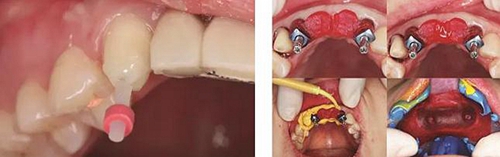

(4)2015年3月—2015年12月:早期修復(fù)伴軟組織誘導(dǎo)成形對(duì)患者制取開窗印模后,使用橋用金屬臨時(shí)基臺(tái),制作聚甲基丙烯酸甲酯(PMMA,登士柏公司,德國(guó))經(jīng)CAD/CAM切削的臨時(shí)修復(fù)橋體,戴入臨時(shí)修復(fù)體對(duì)牙齦軟組織進(jìn)行誘導(dǎo)成形,采用動(dòng)態(tài)加壓技術(shù),最初緩慢戴入臨時(shí)修復(fù)體,撐開牙齦軟組織袖口,擠壓粘膜,粘膜受到擠壓后缺血變白,10min內(nèi)可恢復(fù)為粉紅色。臨時(shí)修復(fù)體為縱向螺絲固位,便于拆卸調(diào)改形態(tài),囑患者勿用臨時(shí)修復(fù)體咬物,注意口腔衛(wèi)生,用牙線或沖牙器等將種植體周圍清潔干凈,每月進(jìn)行復(fù)查,不斷調(diào)改臨時(shí)冠的穿齦形態(tài),讓出軟組織生長(zhǎng)空間,直至誘導(dǎo)牙齦形成類似于天然牙的穿齦袖口形態(tài)。其中在早期修復(fù)3月時(shí),通過打開修復(fù)體間的三角間隙,以讓出齦乳頭生長(zhǎng)的空間;在早期修復(fù)7月時(shí)對(duì)22位點(diǎn)唇側(cè)牙齦根方的軟組織增生物進(jìn)行刮除并縫合,同時(shí)將修復(fù)體的橋體部位調(diào)磨成卵圓形的蓋嵴部并高度拋光,以獲得良好的橋體部軟組織形態(tài),形成健康、連續(xù)且協(xié)調(diào)的軟組織輪廓。

圖17 CBCT測(cè)量骨量變化 圖18 早期修復(fù)戴牙當(dāng)天

圖21 早期修復(fù)3月 圖22 早期修復(fù)3月打開三角間隙

圖23 早期修復(fù)4月 圖24 早期修復(fù)7月切除軟組織增生后

圖25 早期修復(fù)7月調(diào)改橋體部形態(tài)為卵圓形并高度拋光 圖26 早期修復(fù)8月

圖27 早期修復(fù)8月調(diào)改后 圖28 早期修復(fù)10月